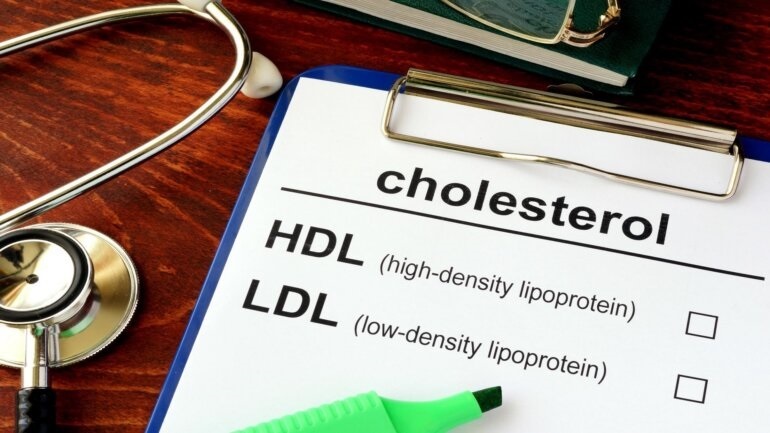

Τα αποτελέσματα της τρέχουσας μελέτης υποδηλώνουν ότι ακόμη και οι σχετικά χαμηλές συγκεντρώσεις PFAS στο αίμα σχετίζονται με δυσμενή προφίλ λιπιδίων του αίματος.